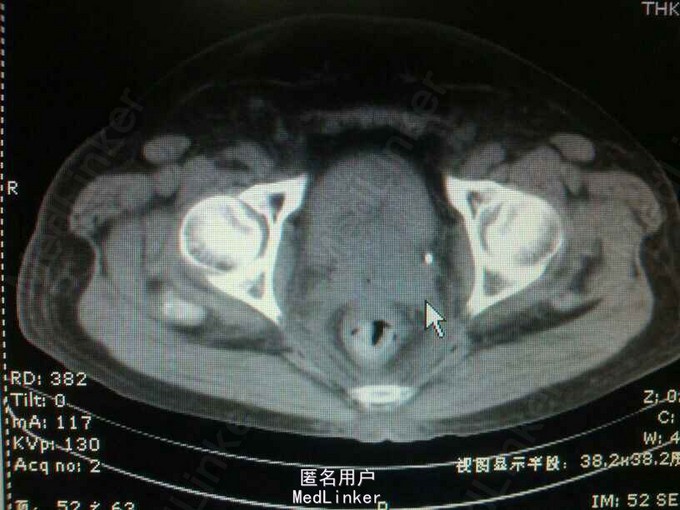

55岁,女性,宫颈癌放疗后两年,阴道出血半年,少尿20天

双肾区叩痛(+-),耻骨上区皮肤增厚,无明显压痛!会阴及双下肢水肿明显! 辅助检查:ct:双肾轻度积水,双侧输尿管全程扩张。膀胱充盈,伴大量血凝块!宫颈癌复发!肾功:血肌酐988,钾5.4,

宫颈癌复发侵犯膀胱及双侧输尿管下段。 肾功能衰竭尿毒症期 膀胱内血凝块

宫颈癌侵犯或压迫双侧输尿管情况较常见。早期,可留置输尿管支架管引流尿液,保护肾功能。 但,该患者留置输尿管支架管成功的可能性大吗?